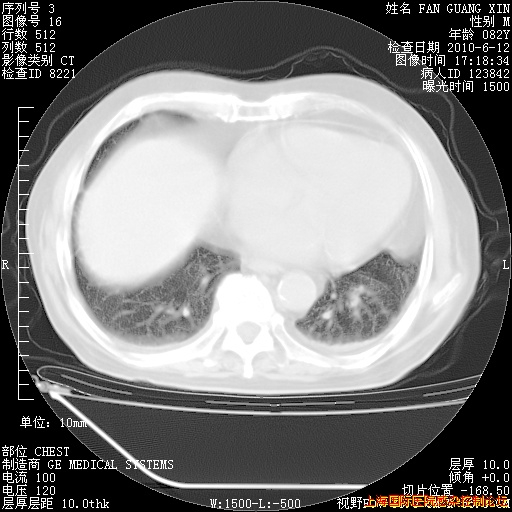

补发6月12日肺部CT肺窗

6月12日肺窗